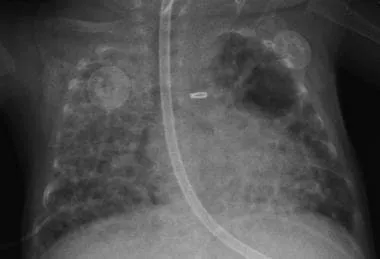

- Impaired Repair & Remodeling: Disrupted healing processes lead to characteristic alveolar simplification (fewer, larger alveoli) and dysmorphic pulmonary vasculature, hallmarks of "new" BPD.

⭐ "New" BPD is characterized more by arrested lung development (alveolar simplification & dysregulated angiogenesis) than the severe airway injury and fibrosis of "old" BPD.